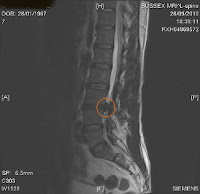

| MRI scan confirms large disc prolapse |

Finally, an MRI scan revealed that Neil was suffering with a prolapsed disc. Steve Morris decided to treat Neil with a programme of IDD Therapy. Neil gained relief within days of treatment.